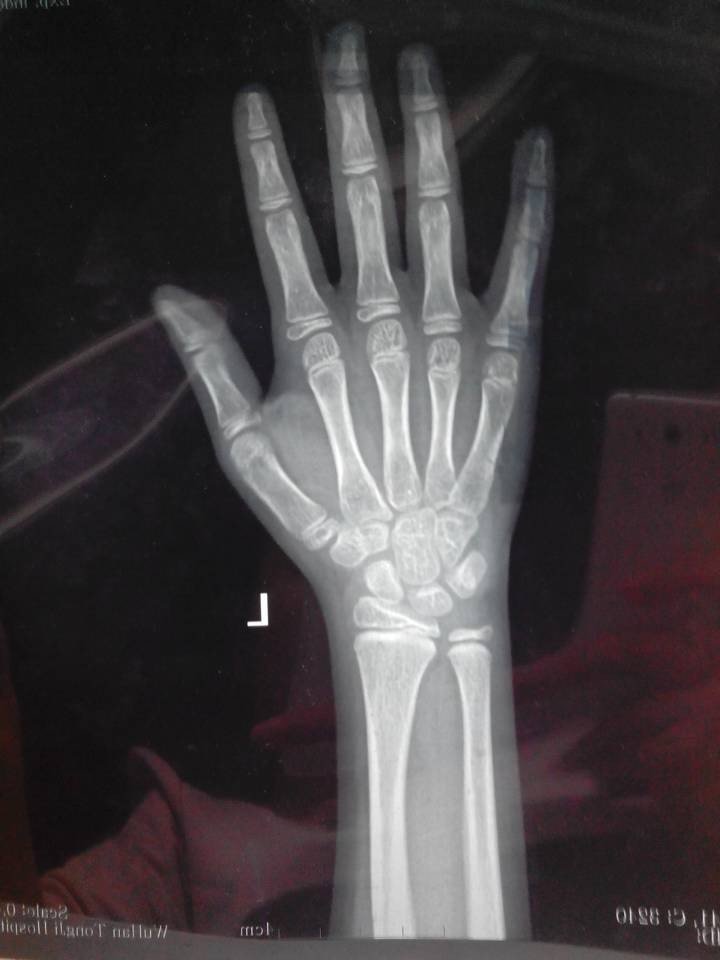

医生你好:我女儿今年8岁半,之前几年她经常喊膝关节痛疼,半年前开始出现乳房发育,半年来乳房小包时消 时长,最近发现没有消了且持续变大。孩子目前身高129.5cm,体重25kg,(孩子爸爸身高171cm,我的身高152cm),提供孩子4月11日刚拍的CT,不知道孩子的情况是否属于儿童性早熟?按目前的状态预测她的成年身高是多高呢?她这种情况需要治疗吗?如果需要治疗,要如何治疗呢?后期的治疗费用大概需要多少呢? 点击展开 匿名用户 2014-04-11 12:31 为您推荐: 其他回答 指导意见: 你好,这个如果孩子没有什么不适就没有问题的 ,.注意观察就可以了.必要时随时去医院进行检查 匿名用户 2014-04-11 15:26 相关问题 今天去给女儿做儿保医生检查出宝宝乳房有小块凝发育了可宝宝才1岁啊上网查了如果单纯乳房长大以后可能会 哺乳期乳房里面有几个小包做了彩超医生说没有事请问是什么原因,而且不痛不痒的 你好医生,我现在乳房一碰就疼是怎么回事啊?

时长,最近发现没有消了且持续变大。孩子目前身高129.5cm,体重25kg,(孩子爸爸身高171cm,我的身高152cm),提供孩子4月11日刚拍的CT,不知道孩子的情况是否属于儿童性早熟?按目前的状态预测她的成年身高是多高呢?她这种情况需要治疗吗?如果需要治疗,要如何治疗呢?后期的治疗费用大概需要多少呢?